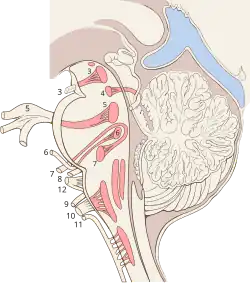

Der Hirnnervenkern des N. trochlearis, der Nucleus nervi trochlearis, liegt im Mittelhirn und schließt sich dem Hauptkern des Nervus oculomotorius kaudal an. Die Fasern steigen vom Trochleariskern in laterokaudaler Richtung ab, ziehen um das zentrale Höhlengrau herum nach dorsal und kreuzen in der Decussatio trochlearis zur Gegenseite, unmittelbar vor ihrem Hirnaustritt. Unterhalb der Colliculi inferiores (bzw. caudales) der Vierhügelplatte und seitlich des Frenulum veli medullaris rostralis (bzw. superioris) tritt der N. trochlearis als einziger Hirnnerv dorsal aus dem Gehirn.

In der Cisterna ambiens des Subarachnoidalraums windet er sich seitlich um den Hirnschenkel (Pedunculus cerebri) an die Basis des Hirnstamms und verläuft hier zwischen der Arteria cerebri posterior und der Arteria superior cerebelli. Etwa in Höhe der Türkensattellehne (Dorsum sellae [turcicae]) durchsetzt er am Rand des Tentoriumschlitzes (Incisura tentorii) die Dura und verläuft in der Seitenwand des venösen Sinus cavernosus. Hier liegt der Nervus trochlearis (N. IV) zwischen dem Nervus oculomotorius (N. III) und dem Nervus ophthalmicus (N. V1).

Nach langem intraduralen und dem längsten intrakraniellen Verlauf aller Hirnnerven verlässt der dünne N. IV die Schädelhöhle beim Menschen durch die Fissura orbitalis superior – bei Nicht-Primaten durch die entsprechende Fissura orbitalis, bei Paarhufern durch das Foramen orbitorotundum – und zieht über den Anulus tendineus communis hinweg in der Augenhöhle zu dem einzigen von ihm innervierten Muskel. Den orbitalen Verlauf begleiten auch afferente propriozeptive Fasern, die – wie bei den übrigen äußeren Augenmuskeln – über Verbindungen (Anastomosen) mit dem Nervus ophthalmicus zum Ganglion trigeminale gelangen.[1]